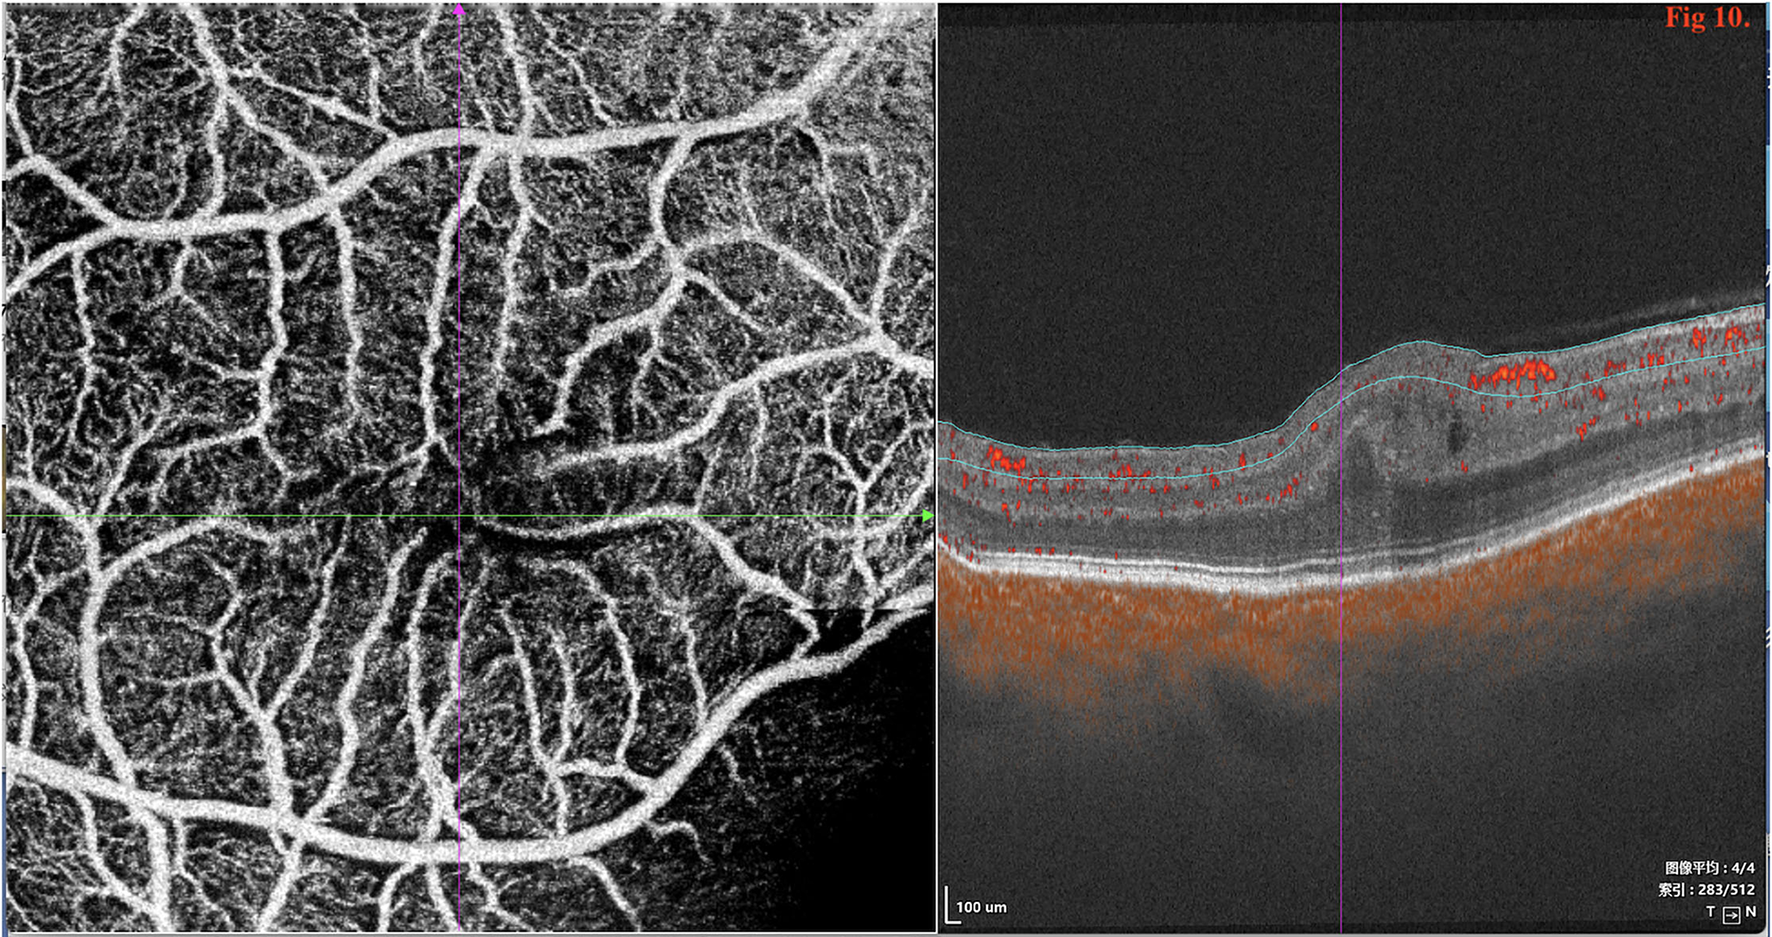

SD/SS-OCTA was performed in 18 type 1 eyes and revealed capillary tortuosity, thickened subfoveal choroid, crowded macular morphology, and macular dysplasia with attenuation of foveal avascular zone (FAZ) (Figure 10). The restoration of photoreceptor and RPE damage, flattening of crowded macular morphology, and expansion of attenuation of FAZ were observed by SS-OCT/OCTA with time during follow-up post-operatively (Supplementary Figures 1, 2).

Figure 10

SD/SS-OCTA (SS-OCT, VG200D, SVision Imaging, Ltd., China) in type 1 revealed that the macular morphology was crowded and showed macular dysplasia with decreased size of foveal avascular zone (FAZ).